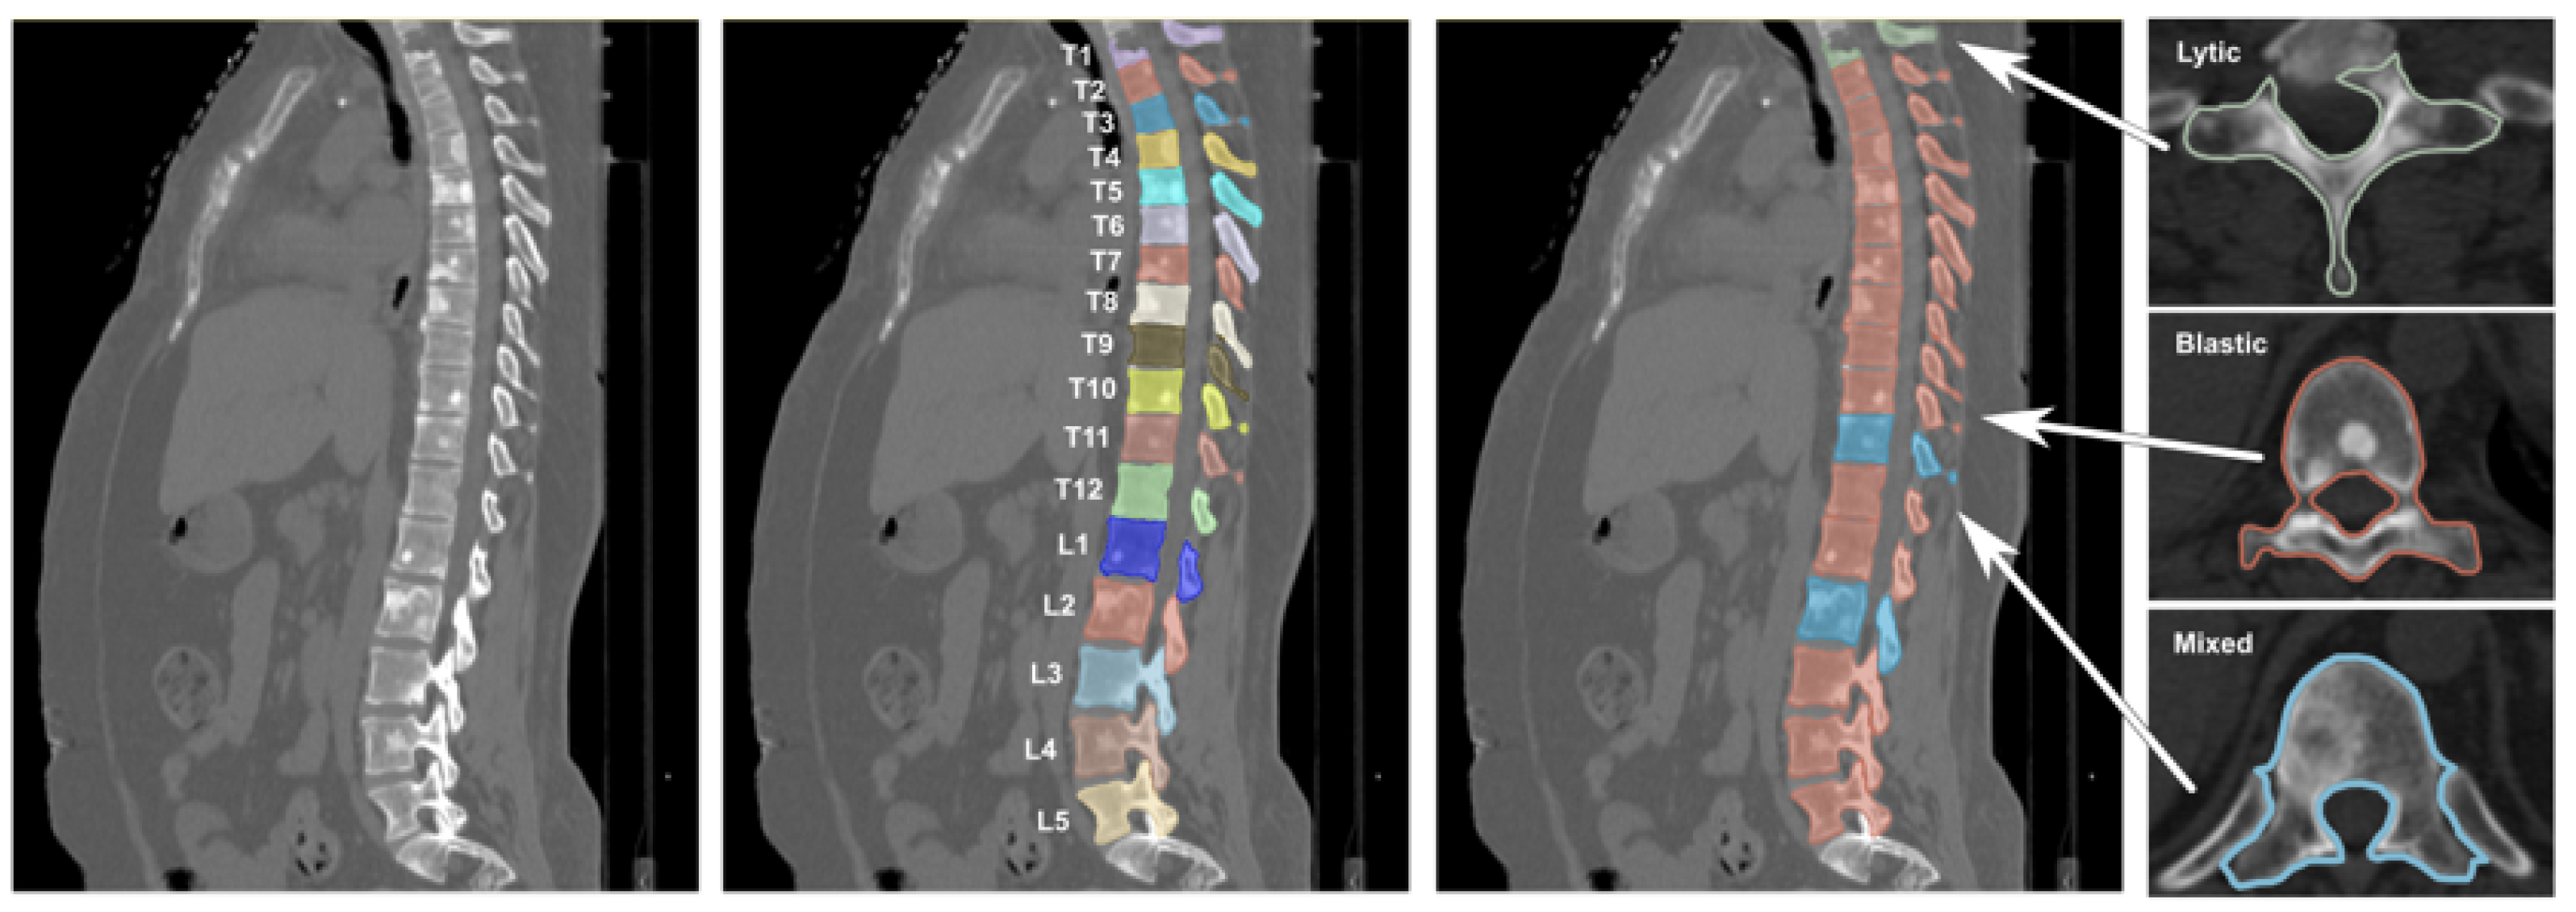

Vertebral labeling followed the Spinal Instability Neoplastic Score (SINS) criteria [28], classifying each vertebra into one of four categories: healthy (no lesion), osteolytic lesion, osteoblastic lesion, or mixed lesion. An example of CT images contained in the Spine-METS-CT-SEG dataset can be seen in Figure 2.

Figure 2. Sagittal and axial CT views of the spine from the Spine-METS-CT-SEG dataset [27]. From left to right: raw CT scan, vertebral segmentation with anatomical labeling, lesion highlighting, and axial slices showing examples of osteolytic (green), osteoblastic (red), and mixed (blue) lesions.

Under physiological conditions, bone homeostasis is tightly regulated by the coordinated interaction of osteoblasts, osteoclasts, and osteocytes; however, the infiltration of malignant cells disrupts this delicate cellular balance, giving rise to abnormal bone remodeling processes that manifest clinically as osteolytic, osteoblastic, or mixed metastatic lesions [8]. These distinct phenotypes exhibit characteristic radiographic signatures, ranging from focal bone destruction in lytic lesions to aberrant bone formation in blastic lesions, resulting in variable attenuation patterns on computed tomography (CT) imaging [9], thus posing significant challenges for automated classification models, particularly in datasets where lesion subtypes co-exist and present overlapping or ambiguous imaging characteristics. Moreover, spinal metastases carry a poor prognosis, with survival typically ranging from three to sixteen months, making treatment largely palliative [10], even though recent improvements in systemic therapies have increased survival and highlighted the need for effective management strategies to preserve neurological function, spinal stability, and overall quality of life [11,12].